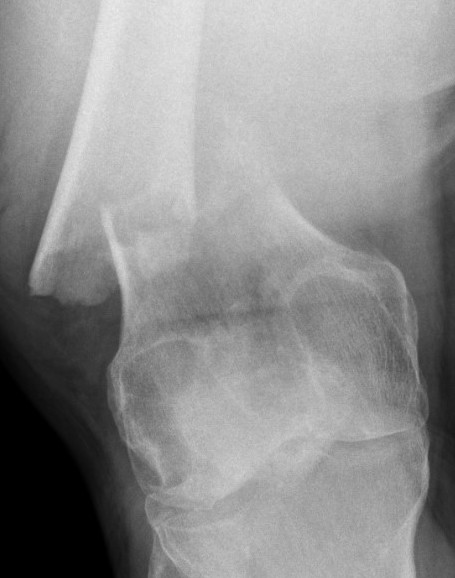

Type C: Complete articular

Xray / CT

AO Type B1 & B2: Partial articular

Definition

Medial or lateral sagittal split